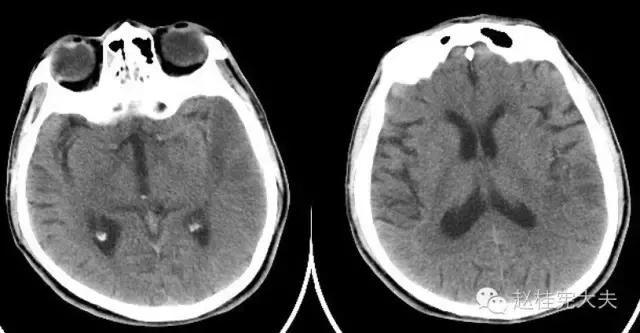

现病史:入院前1周,家属发现患者答非所问,无头痛头晕,无肢体活动障碍,未诊治,入院前2天上午出现构音含糊,晚上言语表达不出,晚上8点至**医院急诊就诊,行颅脑CT示:左侧颞叶不均匀低密度灶,考虑为脑梗死,予以“醒脑静、依达拉奉、血栓通”等治疗,次日早上家属发现患者右侧肢体活动不灵活,持物困难,言语表达困难,不讲话,当时无饮水返呛,入院前1天到我院急诊就诊,当时查体NIHSS7分(面瘫1,右上肢肌力2,右下肢肌力1,感觉1,构音障碍1,失语1),GCS15分。

入院前1天的头颅CT:

定位诊断:混合性失语,定位于左侧大脑半球语言中枢(运动和感觉),右侧中枢性面舌瘫,定位于左侧面神经核团以上,右侧上下肢肌力下降,病理征阳性,定位于左侧锥体束。感觉、视野查体无法配合,暂无相应定位考虑。综合考虑,定位于左侧大脑中动脉分布范围。头颅CT:左侧颞叶片状低密度影,左侧大脑中动脉下干支配区,支持临床定位。

定性诊断:结合57岁,男性,急性病程,逐渐加重,进展性右侧肢体无力、混合性失语。头颅CT:左侧颞叶片状低密度影。脑梗死为首先考虑,左侧大脑中动脉支配区,大动脉粥样硬化型。尽管患者本人无高血压、糖尿病等危险因素,但患者母亲有中风、糖尿病史,存在家族中风危险因素,故待完善血生化及血管等卒中危险因素筛查。入院后继续急诊抗血小板、降脂稳定斑块及脑保护治疗。